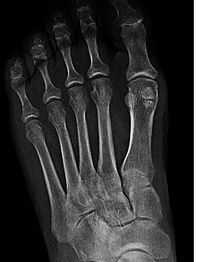

دنیای اطلاعات: استخوانهای سزموئید (sesamoid bones) استخوانهای کوچکی هستند که در لابه لای وتر اتصال عضلانی وتری قرار دارند. استخوانهای سزموئید باعث افزایش مزیت مکانیکی و محافظت از اتصالات عضلانی وتری میشوند. البته جزءدستهبندی اصلی استخوانها قرار ندارند.

استخوان سزموئید استخوانی تعبیه شده در یک تاندون یا یک عضله است. با توجه به اندازه کوچک اغلب سزموئیدها نام (دانه کنجدی) از کلمه لاتین “sesamum” (sesame seed) مشتق شده است، در بعضی اوقات این استخوان به فشارهای وارده واکنش نشان می دهد.

استخوان سزموئید